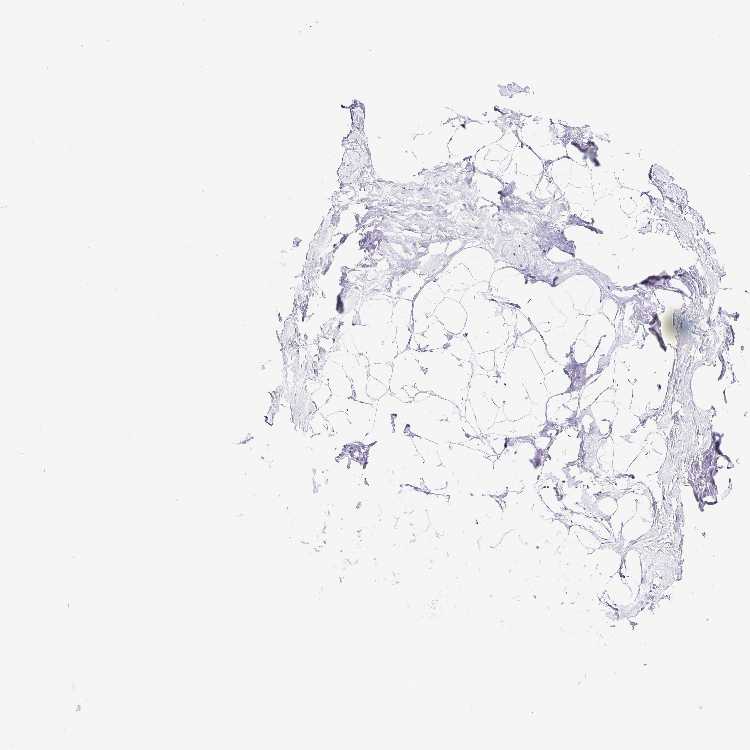

BREAST - Antibody stainingi

Antibody staining in the annotated cell types in the current human tissue is reported as not detected, low, medium, or high, based on conventional immunohistochemistry profiling in selected tissues. This score is based on the combination of the staining intensity and fraction of stained cells.

Each image is clickable and will lead to virtual microscopy that enables deeper exploration of all samples and also displays staining intensity scores, fraction scores and subcellular localization as well as patient and tissue information for each sample.

Antibody HPA051368Antibody HPA061671

Adipocytes Not detectedNot detected

Glandular cells Not detectedNot detected

Myoepithelial cells Not detectedNot detected